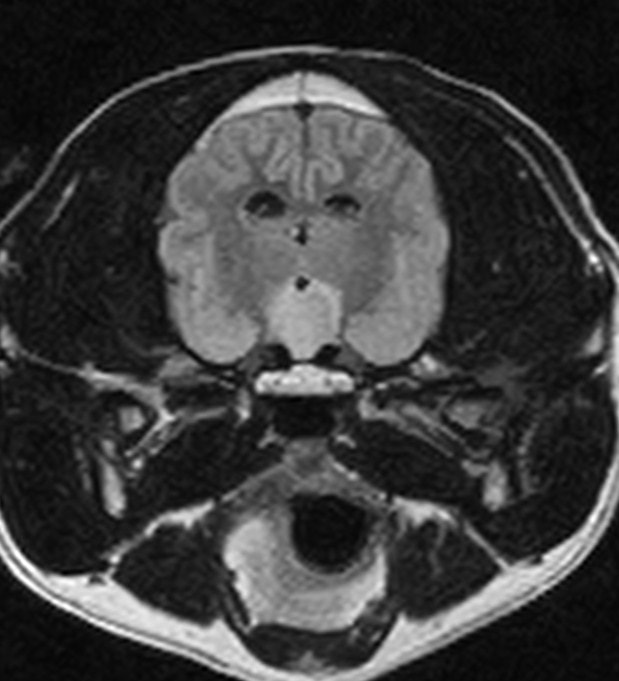

MRI画像:クッシング症候群の犬の下垂体腺腫

上記のような症状が認められた場合、まず血液検査・腹部X線検査などにより、除外診断を行います。臨床症状を含め、特徴的な所見が認められた場合、クッシング症候群の確定診断のためACTH負荷試験と呼ばれる検査を行います。状況により、エコー検査、CT/MRI検査を行い、コルチゾール分泌に関わる下垂体や副腎の状態を確認します。クッシング症候群と診断された場合は、お薬によるコントロール、原因によっては外科手術などが必要となってきます。